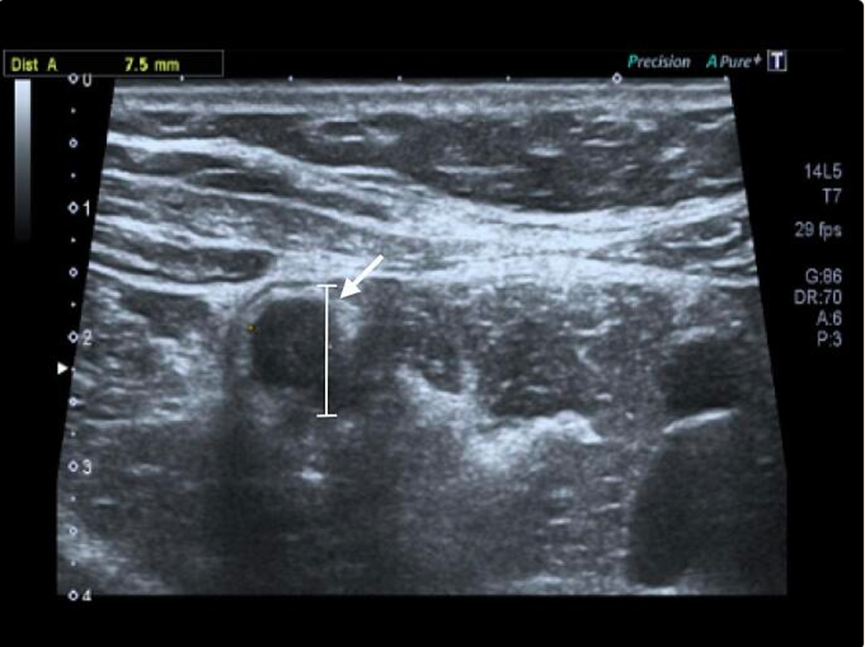

白细胞计数正常,无其他病理实验室检查结果。腹部超声检查显示,右下腹直径7.5mm的增厚阑尾,与脂肪链和游离液相关(图1)。CT扫描显示,阑尾增厚(图2)。

图1. 腹部超声显示右下腹直径 7,5 毫米的增厚阑尾(白色箭头),与脂肪链和游离液有关